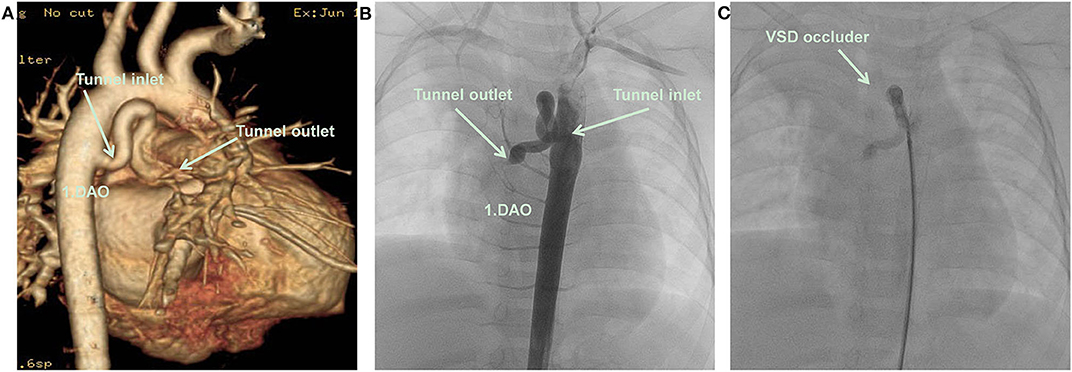

A 9.2 kg 11-month-old Chinese girl was admitted to the Kunming Children's Hospital for a cardiac murmur. The parents of the child reported no symptoms or growth retardation, and there was no family history of congenital heart defects. A 2/6 systolic murmur was heard at the upper right sternal border. A routine echocardiography was performed, and a diagnosis of partial anomalous pulmonary venous connection was suspected (Figure 1A). Subsequently, computerized tomography angiography (CTA) demonstrated an abnormal blood vessel from the descending aorta, ascending across the left main bronchus, and then descending to end in the right atrium (Figure 2A).

Figure 2. (A) CTA: An abnormal blood vessel developed from descending aorta, and zigzagged to the right atrium. (B) Cardiac catheterization: An abnormal blood vessel developed from descending aorta, and zigzagged to the right atrium. (C) A VSD occluder has been placed at the inlet of tunnel, there was no obvious shunt revealed by aortography after closure. DAO, descending aorta; RA, right atrium; VSD occluder, ventricular septal defect occluder.

The patient underwent cardiac catheterization. The right femoral artery was cannulated using 5 Fr sheaths, and the patient was heparinized (100 U/kg). Aortography in the descending aorta demonstrated that an abnormal blood vessel was present from the right anterior wall of the descending aorta at the height equal to that of the 4–5th thoracic vertebrae and followed a tortuous course to the right atrium. The diameter of the tunnel inlet was 4 mm and that of the opening into the right atrium was only 1 mm (Figure 2B). An occlusion was performed using a 5 mm (waist diameter 5 mm, length 5 mm) new VSD occluder (Starway Medical Technology, Beijing, China) from the arterial side using a 4 Fr long sheath (Starway Medical Technology).

A 260 cm 0.032-inch super smooth guidewire (Starway Medical Technology) was inserted from the descending aorta side in the direction of blood flow to the distal tunnel. A 4 Fr Cobra catheter was guided into the tunnel, and the smooth guidewire was withdrawn and replaced with a 260 cm 0.035-inch stiff guidewire (Starway Medical Technology) to establish a tunnel-descending femoral orbital artery in the right aorta. The 4 Fr long sheath was inserted along the stiff guidewire. A 5 mm new VSD occluder was loaded, the distal disc of the occluder was fixed at the U-shaped bend of the tunnel, and the waist and proximal disc were fixed in the ascending branch of the U-shaped bend of the tunnel. No obvious shunt was revealed by aortography after device placement (Figure 2C). No procedural complications occurred and neither an antiplatelet nor antibiotic treatment was used after the procedure. An abnormal color flow was not seen on the postprocedural cardiac echocardiography. At 6 months of follow-up, the patient remained well, and no residual shunt was found using the echocardiogram (Figure 1B). The patient's parents provided informed consent for the patient's information including supporting images to be published.